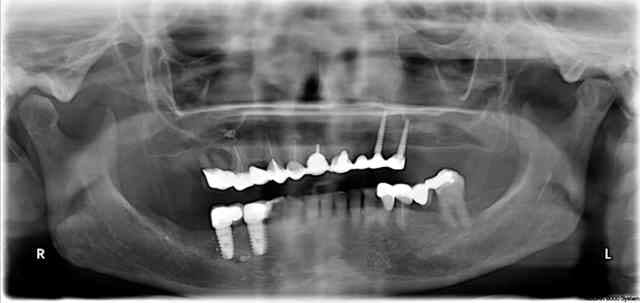

il manquait la pano

Pano 3d positdental egcieb - Eugenol